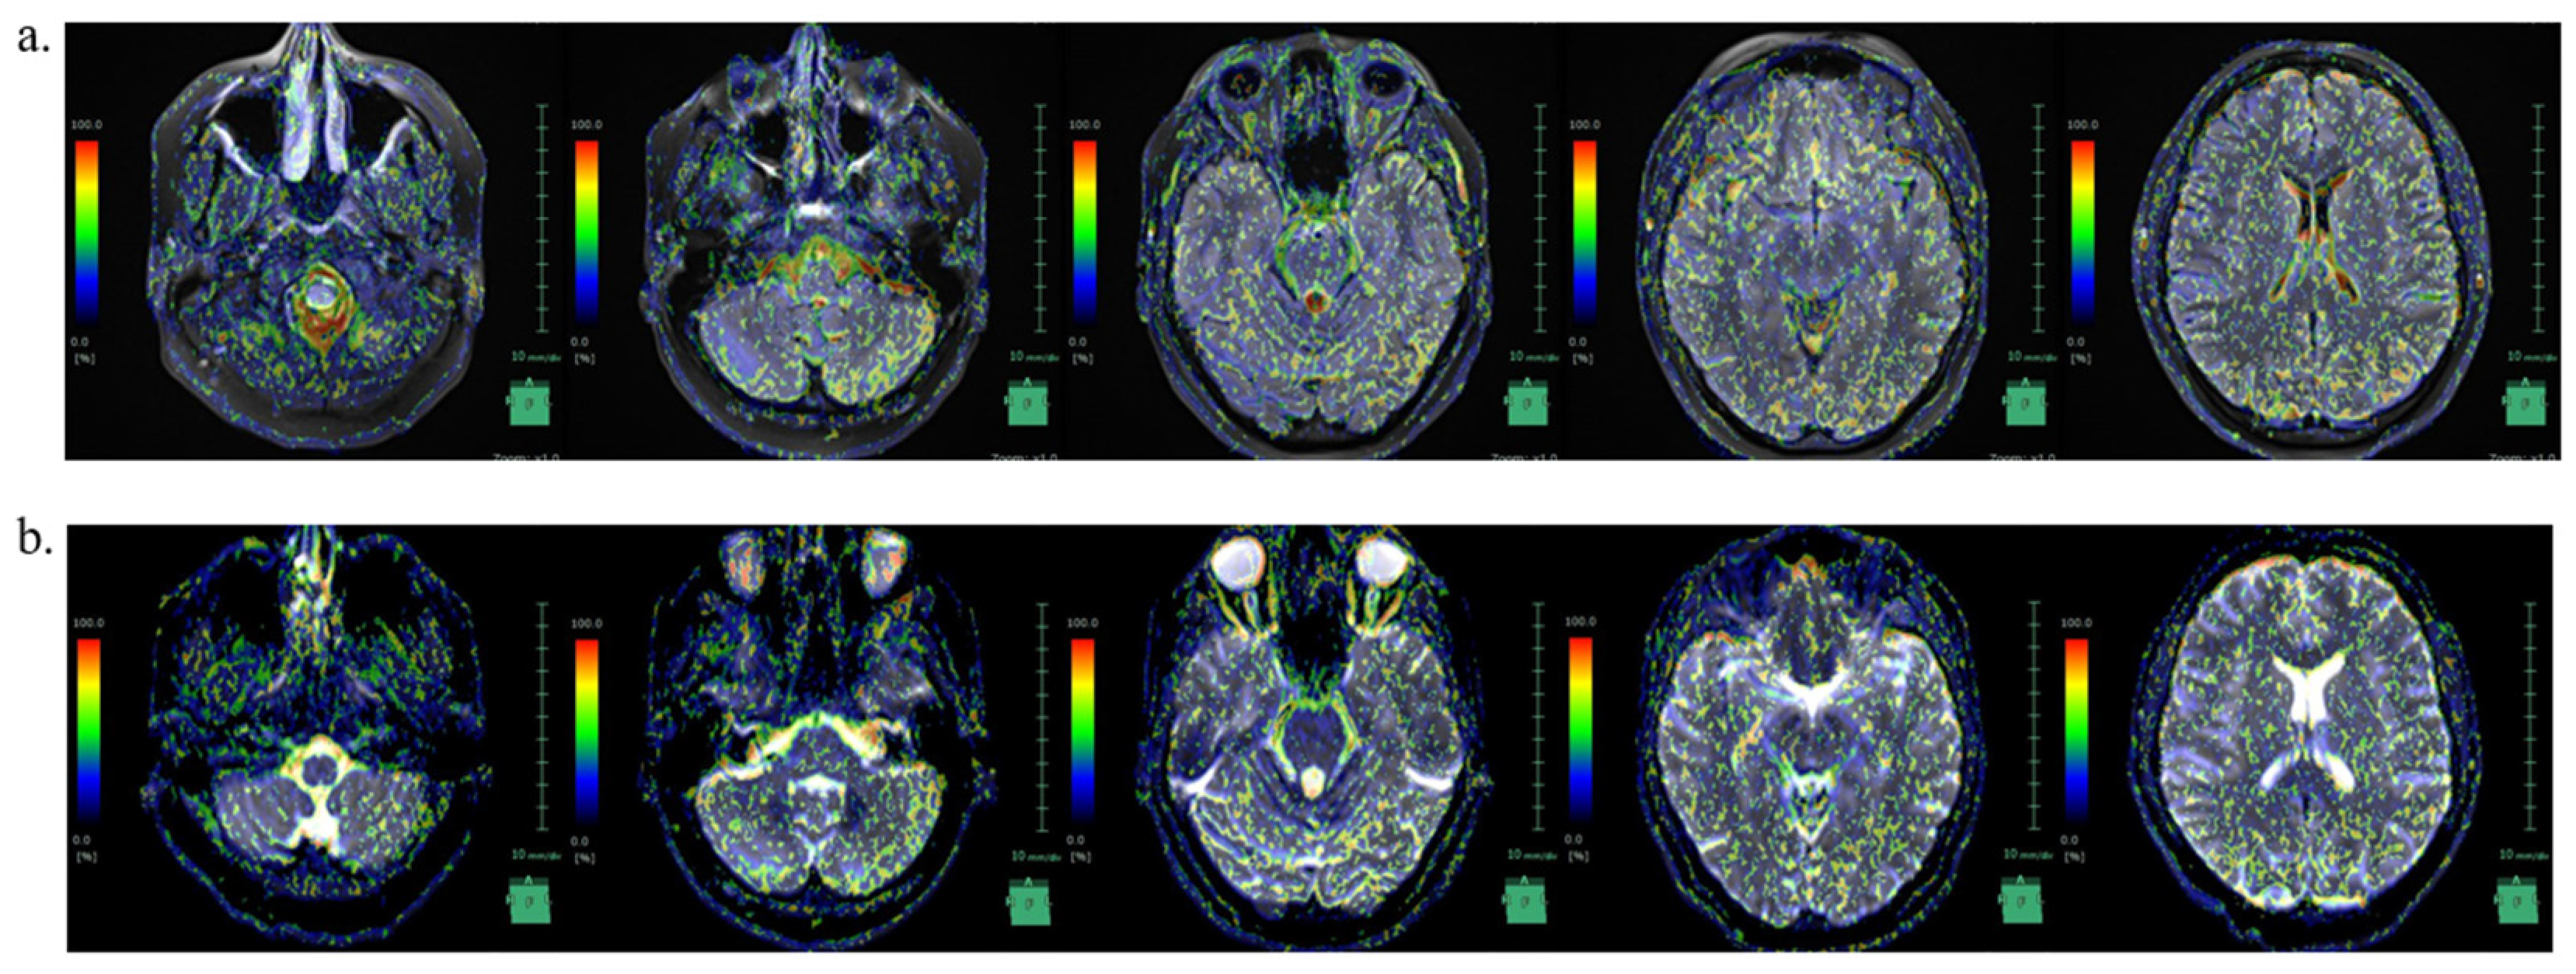

A Case of Idiopathic Intracranial Hypertension Complicated with both Infratentorial and Supratentorial Cortical Superficial Siderosis: Novel Imaging Findings on Intravoxel Incoherent Motion Magnetic Resonance Imaging Offering Clues to Pathophysiology

2. Case Description

3.4. CSF Circulation in IIH with SS

- Yamada, S.; Hiratsuka, S.; Otani, T.; Ii, S.; Wada, S.; Oshima, M.; Nozaki, K.; Watanabe, Y. Usefulness of intravoxel incoherent motion MRI for visualizing slow cerebrospinal fluid motion. Fluids Barriers CNS 2023, 20, 16. [Google Scholar] [CrossRef] [PubMed]

| IICP State | Decreased ICP State | |

|---|---|---|

| Foramen magnum | 70.6 | 86.9 |

| Right foramen of Luschka | 44.3 | 89.1 |

| Left foramen of Luschka | 49.2 | 91.9 |

| Foramen of Magendie | 96.1 | 90.4 |

| Medullary cistern | 75.5 | 52.6 |

| Fourth ventricle | 87.4 | 77.3 |

| Right cerebellopontine angle | 11.7 | 97.7 |

| Left cerebellopontine angle | 96.8 | 59.7 |

| Right inferior horn of lateral ventricles | 11.5 | 10.1 |

| Left inferior horn of lateral ventricles | 4.1 | 6.8 |

| Interpeduncular cistern | 66.1 | 34.4 |

| Subarachnoid space of right temporal lobe | 94.8 | 13.1 |

| Subarachnoid space of left temporal lobe | 33.3 | 22.1 |

| Right sylvian fissure | 93.8 | 4.1 |

| Left sylvian fissure | 97.3 | 4.8 |

| Third ventricle | 80.8 | 57.5 |

| Right anterior horn of lateral ventricles | 98.6 | 9.6 |

| Left anterior horn of lateral ventricles | 1 | 98.9 |

| Right foramen of Monro | 58.3 | 3.5 |

| Left foramen of Monro | 96.2 | 1.3 |

| Right body of lateral ventricles | 89.9 | 47 |

| Left body of lateral ventricles | 99.2 | 0.9 |

| Subarachnoid space of right frontal lobe | 94.3 | 47 |

| Subarachnoid space of left frontal lobe | 98.7 | 98.2 |

| Right central sulcus | 86.7 | 90.8 |

| Left central sulcus | 94.4 | 53.6 |

| Subarachnoid space of right parietal lobe | 69 | 96.5 |

| Subarachnoid space of left parietal lobe | 83.5 | 96 |